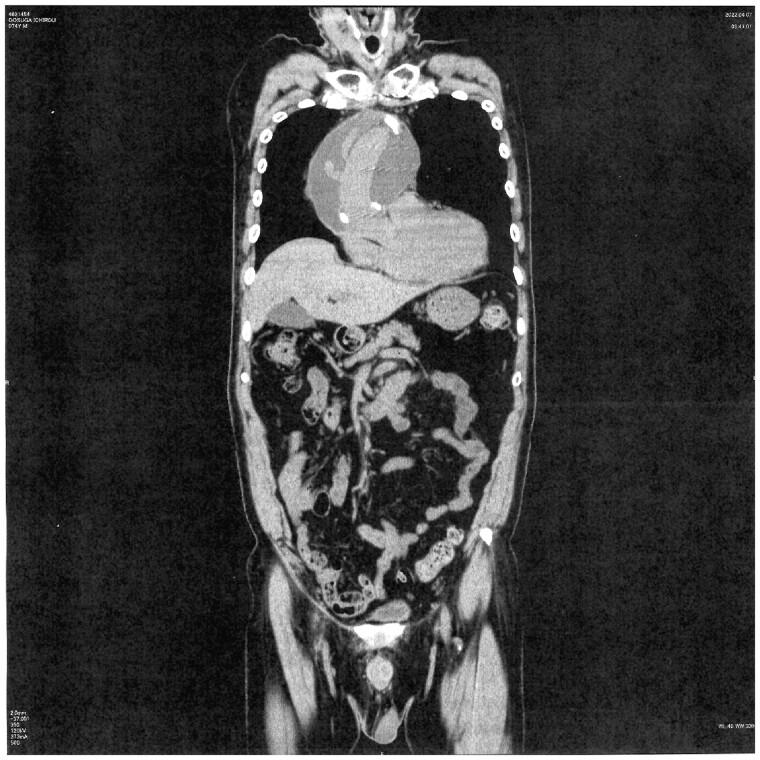

Eighty-two patients who underwent either ascending aortic replacement or aortic arch replacement between 2016 and 2022 in our institution were enrolled in the present study. Postoperative computed tomography scans were performed to detect fluid capsules with a diameter ≥3.0 cm and radiodensity ≤25 Hounsfield units. Patients who did and who did not develop PGS formation were compared. Variables with a statistically significant difference between these groups were included in a multiple logistic regression analysis along with other factors associated with PGS in the literature.

RESULTS

The incidence rate of PGS was 14.6% (12/82). The average radiodensity of the mass was 16.6 ± 6.3 Hounsfield units. The average onset of PGS was 8.5 months post-surgery. Multivariate logistic regression analysis revealed that ejection fraction [odds ratio (OR): 1.25, 95% confidence interval (CI): 1.03-1.50, P = 0.021], aortic dissection (versus degenerative aortic aneurysm) (OR: 6.61, 95% CI: 1.35-32.4, P = 0.02) and warfarin use (OR: 6.67, 95% CI: 1.19-37.1, P = 0.03) significantly contributed to mediastinal PGS after thoracic aortic surgery.